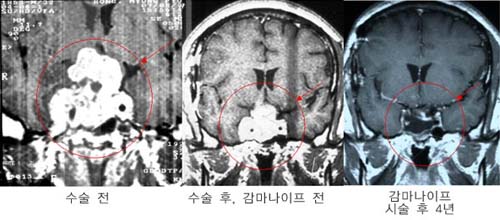

³úµ¿Á¤¸Æ

񃀁

³ú

±íÀº °÷¿¡ À§Ä¡ÇÏ¿© ³úÃâÇ÷À» ÀÏÀ¸Å² 17¼¼

¿©ÀÚȯÀÚÀÇ MRI ¹× ³úÇ÷°üÃÔ¿µ¼ú »çÁø.

³úÀÇ

±íÀº °÷¿¡ ³úµ¿Á¤¸Æ±âÇüÀÌ À§Ä¡ÇÏ¿© ¼ö¼úÀû

Ä¡·á°¡ ºÒ°¡´ÉÇÏ¿´À¸³ª °¨¸¶³ªÀÌÇÁ ½Ã¼ú

ÈÄ 24°³¿ù°¿¡ ¸ðµÎ ¿ÏÄ¡µÇ¾ú´Ù

°æ·ÃÀ»

ÁÖ¼Ò·Î ÀÔ¿øÇÑ È¯ÀÚÀÇ MRI ¹× ³úÇ÷°üÃÔ¿µ¼ú

»çÁø.

µ¿Á¤¸Æ±âÇüÀÇ

Å©±â°¡ Ä¿¼ ¼ö¼úÀÇ À§Ç輺ÀÌ ³ô¾Æ °¨¸¶³ªÀÌÇÁ¸¦

°èȹÇÏ¿´´Ù. º´º¯ÀÇ Å©±â°¡ Ä¿¼ °¨¸¶³ªÀÌÇÁ

¹æ»ç¼±¼ö¼úÀ» ¸îÂ÷·Ê¿¡ ³ª´©¾î¼ ½ÃÇàÇÏ·Á

ÇÏ¿´À¸³ª ÇÑÂ÷·ÊÀÇ °¨¸¶³ªÀÌÇÁ ½Ã¼ú ÈÄ

24°³¿ù° ¸ðµÎ ¿ÏÄ¡µÇ¾ú´Ù.

º´º¯ÀÇ

Å©±â°¡ Å« µ¿Á¤¸Æ±âÇüÀÇ °æ¿ì °¨¸¶³ªÀÌÇÁ

¹æ»ç¼±¼ö¼úÀ» ¸îÂ÷·Ê¿¡ ³ª´©¾î¼ ½ÃÇàÇÏ¿©¾ß

Çϳª ÀϺΠȯÀÚÀÇ °æ¿ì ÇÑÂ÷·ÊÀÇ °¨¸¶³ªÀÌÇÁ

½Ã¼ú·Îµµ ¿ÏÄ¡¸¦ º¸¿´´Ù